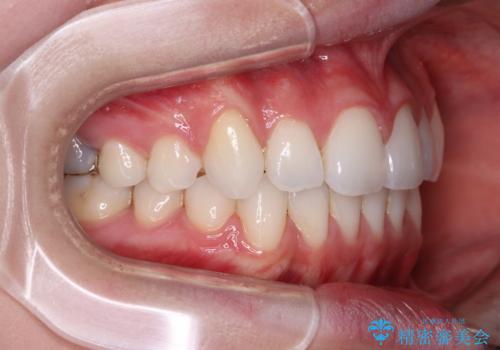

補助装置を使用したことで、口元が突出することもなく、スムーズに仕上げることができました。